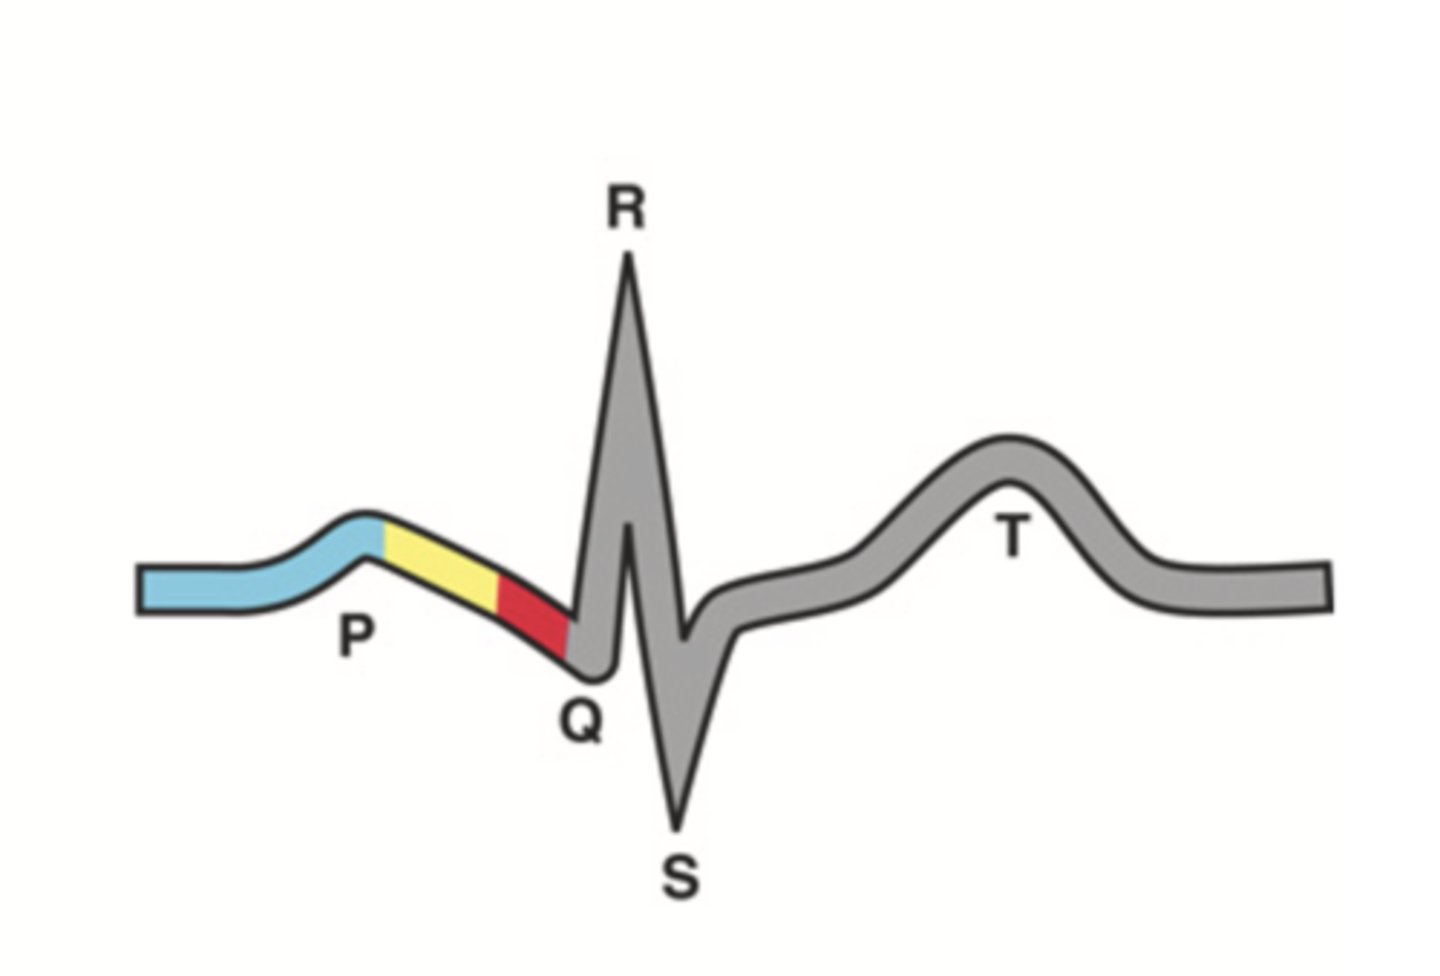

4 Parts of the Heart's Conduction System

- Sinoatrial (SA) node

- Atrioventricular (AV) node

- Bundle of His

- Purkinje fibers

Sinoatrial (SA) Node

Pacemaker of the heart conduction system, located at the right atrium (light blue)

Atrioventricular (AV) Node

The part that relays electrical impulses from atria into the bundle of his in the heart's conduction system; delayed slightly (yellow)

Bundle of His

Part of the heart's conduction system that transmits the cardiac impulse from the atrioventricular node to the purkinje fibers (red)

Purkinje Fibers

Fibers in the ventricles that transmit impulses to the right and left ventricles, causing them to contract

ECG Waves

- P wave

- P-R interval

- QRS complex

- Q-T interval

- T wave

P Wave

Atrial depolarization

P-R Interval

Atrial contraction

QRS Complex

Ventricular depolarization

Q-T Interval

Ventricular contraction

T Wave

Repolarization of ventricles